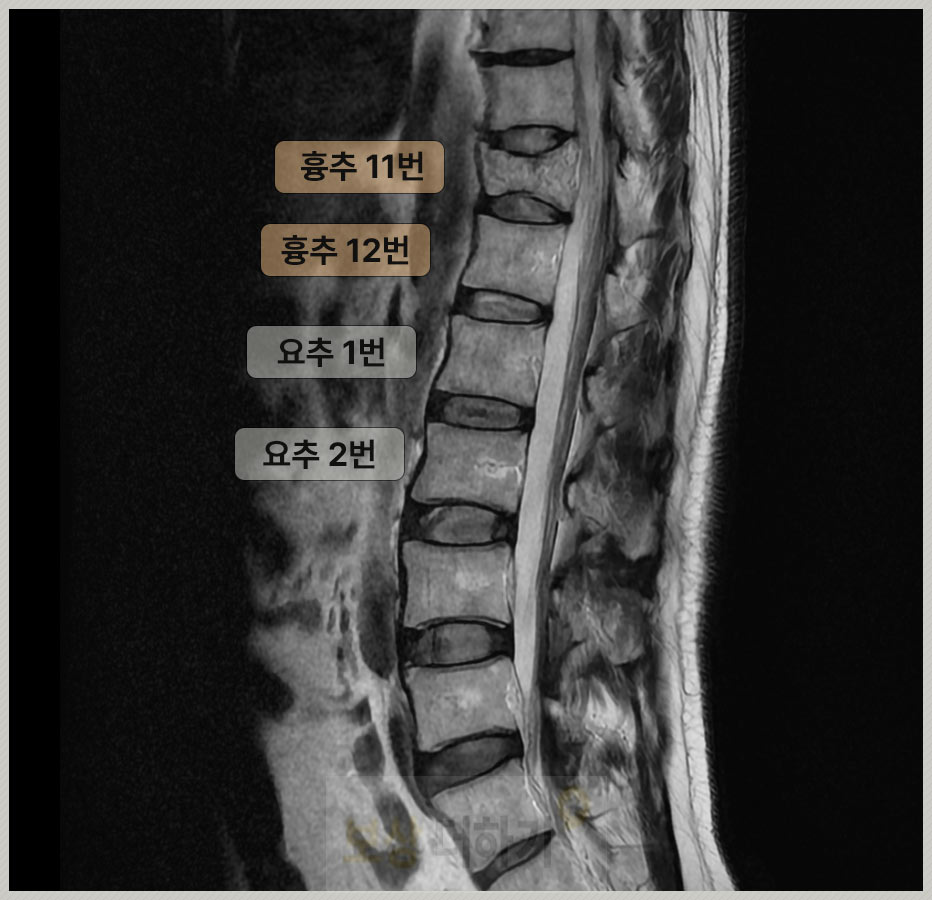

화장실에서 미끄러지면 엉덩방아를 찧는 경우가 정말 많습니다. 이때 충격이 [엉덩이 → 천골 → 요추 → 흉추 하부, 특히 11, 12번]으로 전달이 되죠. 따라서 이 부위에 골절이 일어나기 쉽습니다.

흉추 11번 ~ 12번은 등뼈인 흉추와 허리 뼈인 요추가 연결되는 부위 이 과도기 부위는 충격을 받을 때 힘이 집중되면서 골절이 잘 일어남

P 님 역시 이번 일로 흉추 11번 골절 진단을 받았습니다.